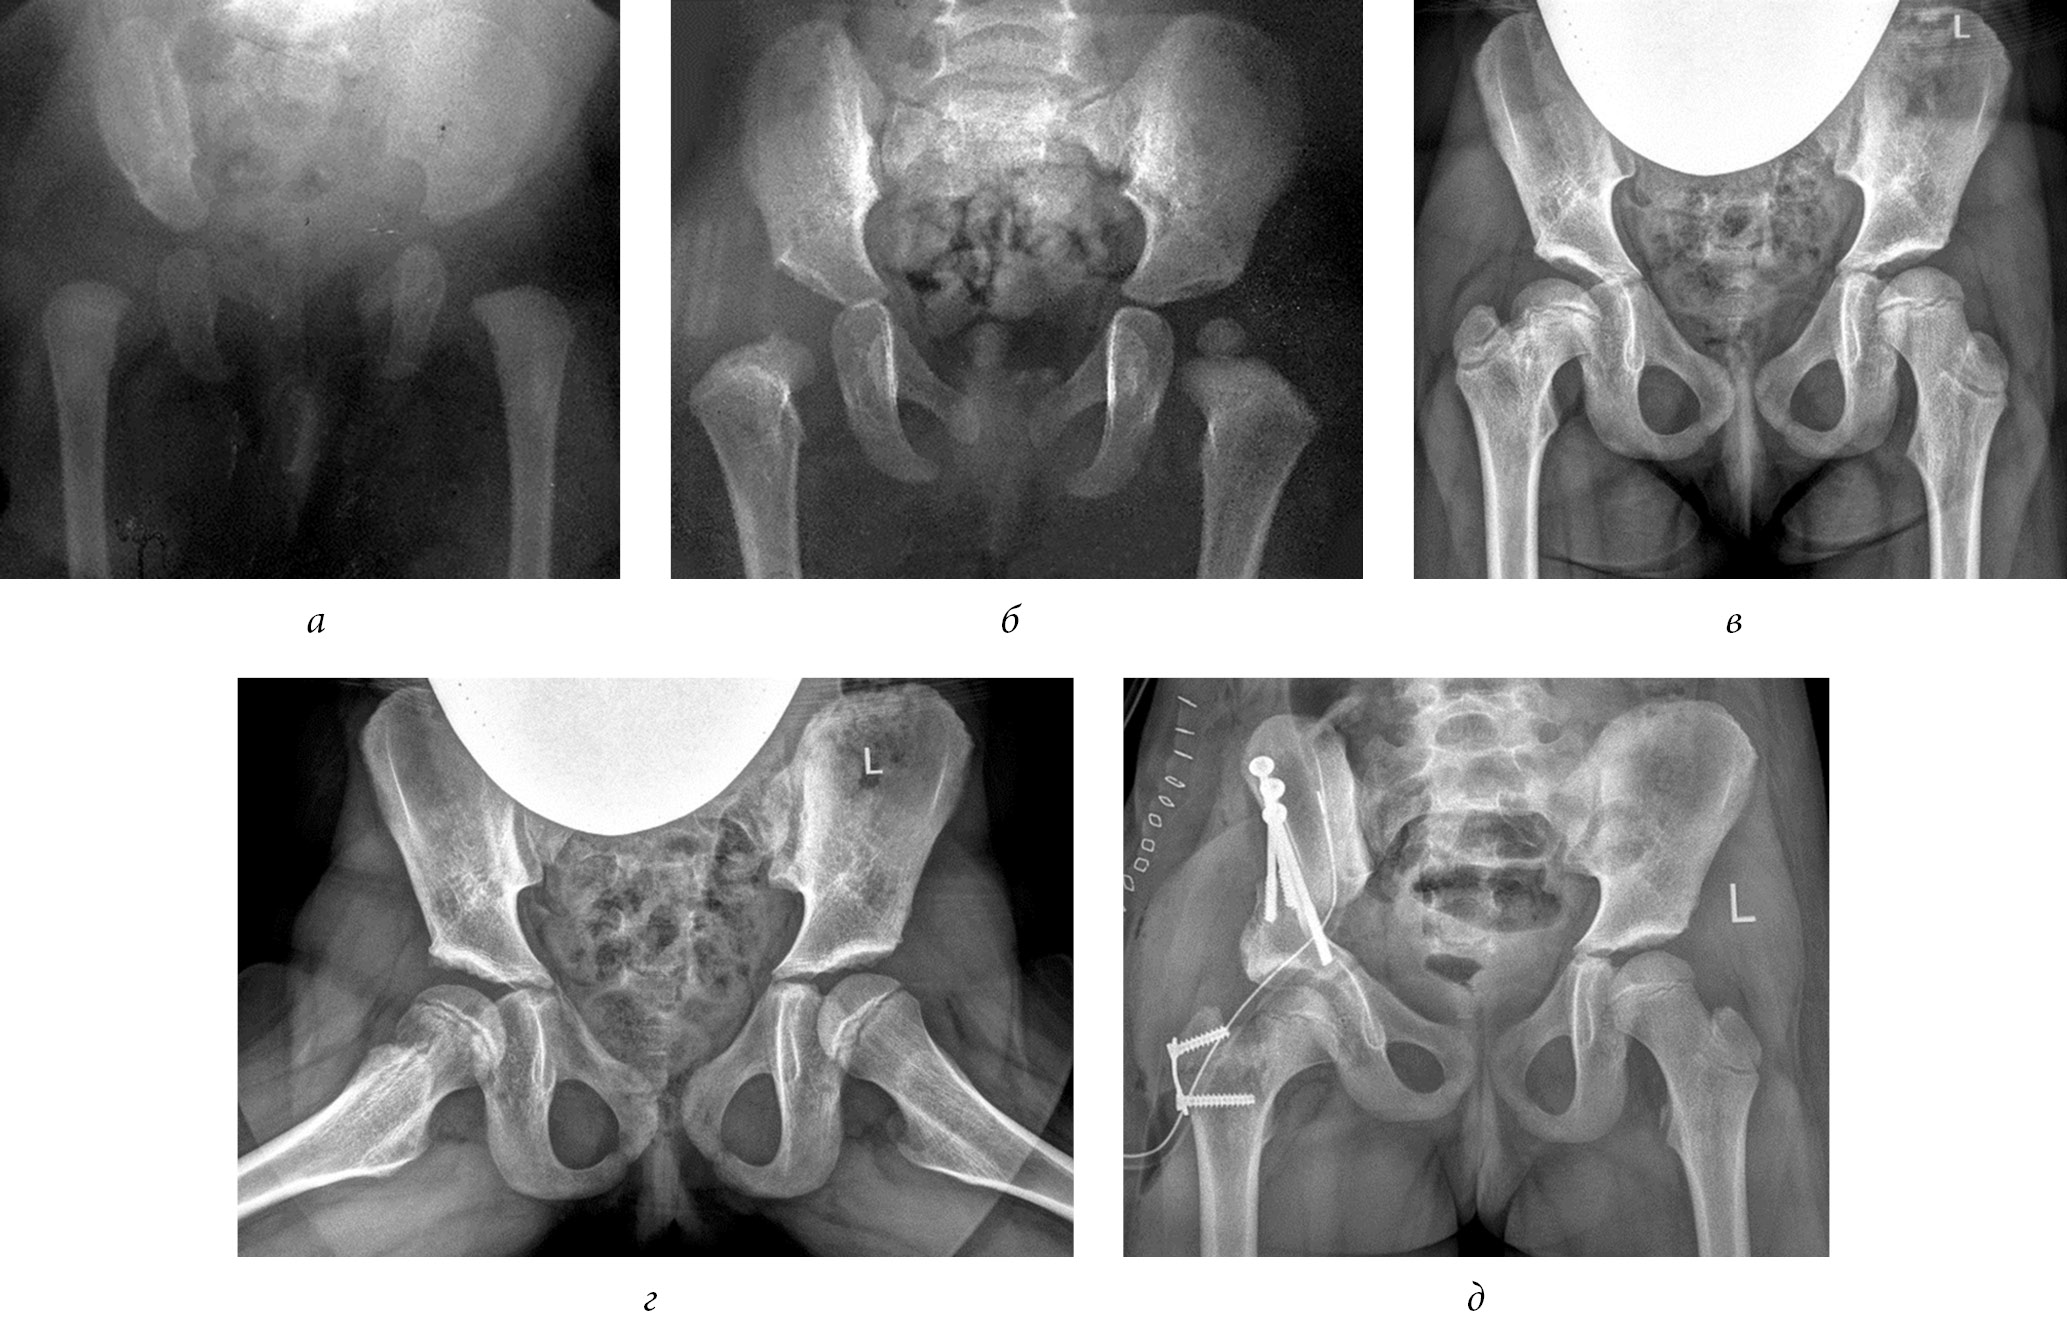

The table shows that the initial ATD value on the affected side was significantly less than that on the intact side (p < 0.05). Over the follow-up period, values of the ATD parameters in the main and control groups almost remained unchanged. Differences between the indicators also did not change, that is, no progressive displacement of the greater trochanter apex in relation to the superior pole of the head was noted. In addition, the mean values of the normal growth of the greater trochanter (TTD index) for the intact and affected joints did not differ initially, that is, the condition of the greater trochanter on the affected side did not progress. During the postoperative follow-up period, the TTD index increased by 10.0 ± 5.5 mm in the healthy hip joint and by 5.08 ± 4.1 mm in the affected hip joint. Thus, based on the changes in the TTD index, surgical treatment slowed the growth of the greater trochanter by 49.3% (p < 0.05). The neck–shaft angle during the follow-up period did not fundamentally change on both the affected and intact sides, with differences in dynamics by no more than 0.9% (p > 0.05) (Fig. 3).

Fig. 3. Radiographs of patient K (9 years old) diagnosed with Perthes disease on the left side but was in the recovery stage: a, before surgery; b, 2.5 years after the trochanteric epiphysiodesis on the left